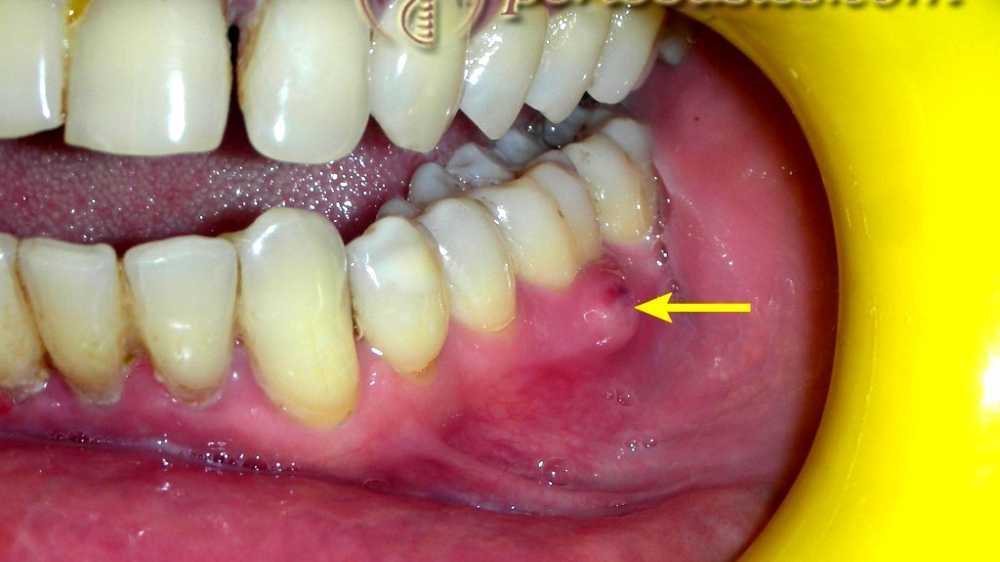

periodontal abscess Abscess Tooth With Crown Dental abscesses are abscesses affecting the teeth and adjacent jaw tissue. Intense toothache or pain in your gums. The infection can affect surrounding tissues and cause severe pain. It happens when bacteria invade your tooth pulp, usually through. A tooth abscess needs appropriate treatment, which can improve symptoms within days. A tooth abscess, also called an oral or dental abscess,. Abscess Tooth With Crown.